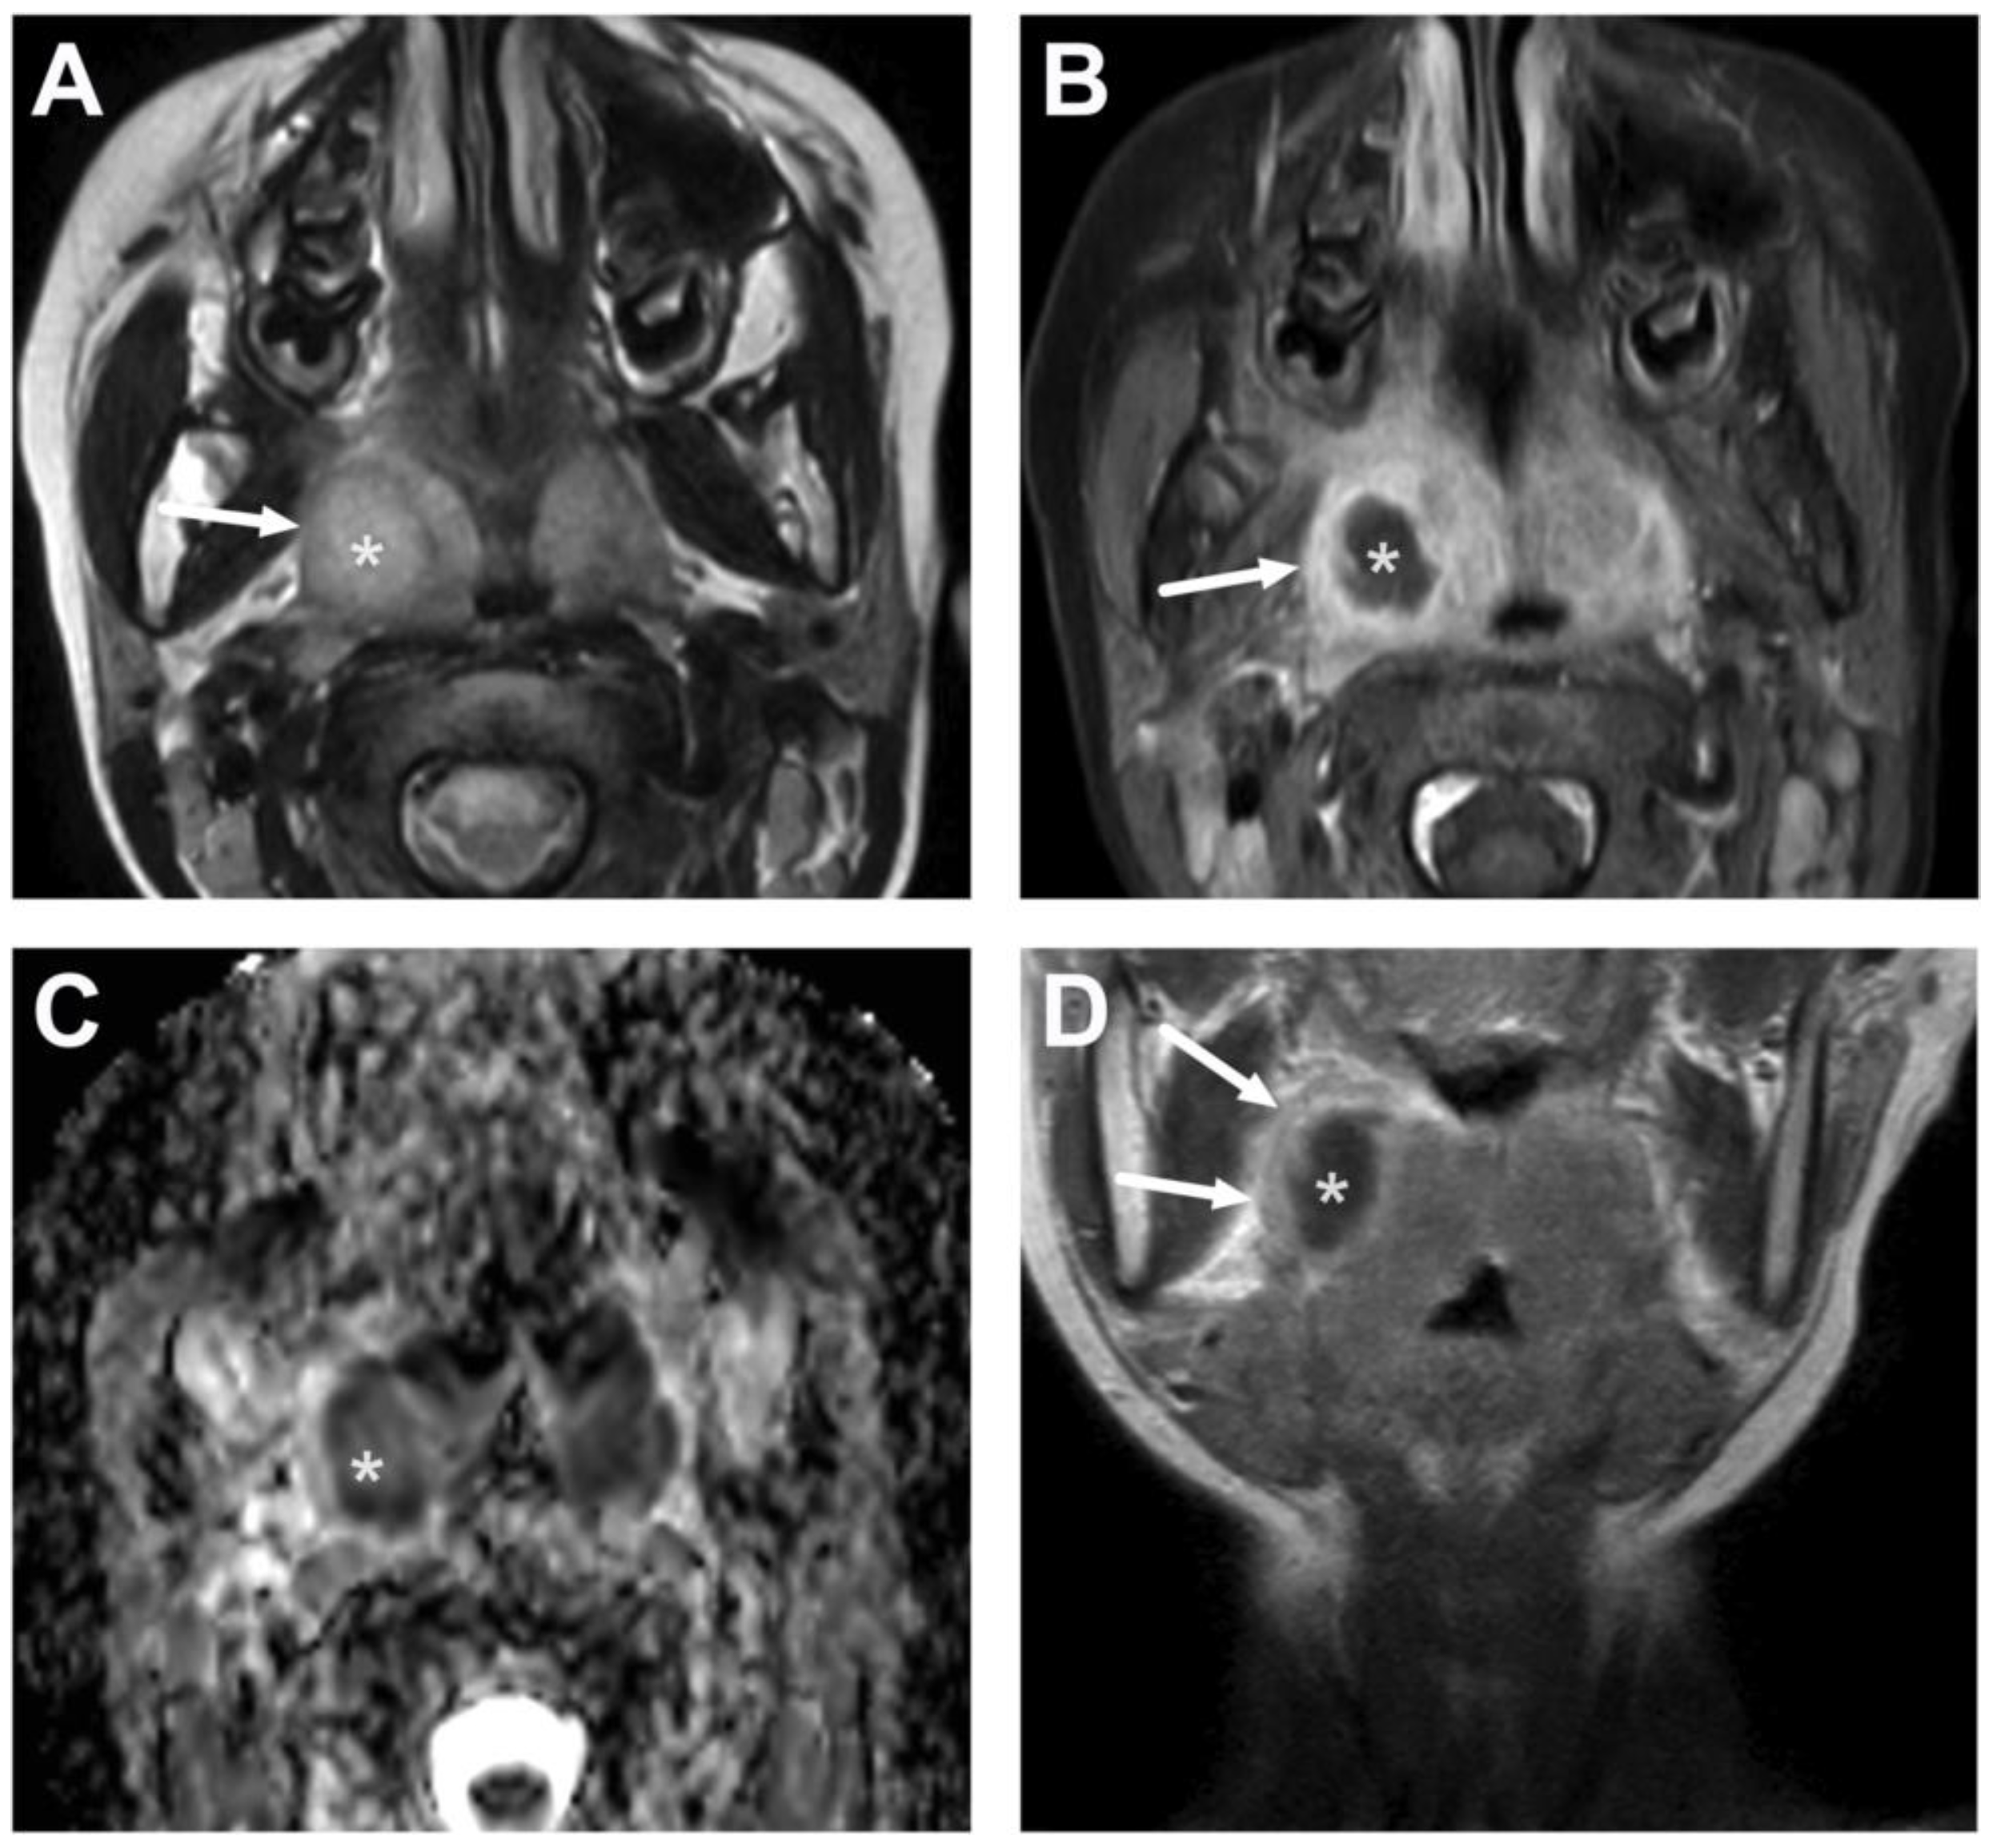

5.1. Lymphadenitis with Purulence vs. Necrosis

5.2. Cystic Masses